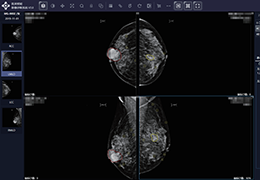

成像智能。

Eclipse 成像智能功能提供强大的处理能力和最佳质量的影像,同时减少质量错误并提高剂量效率。

凭借 AI、专有算法和先进的影像处理能力,提供出色的影像质量和无与伦比的诊断信心。

与标准影像处理相比,智能降噪功能可使客户降低辐射剂量,而不会损失影像质量。这在新生儿和儿科成像中尤其重要,在这种情况下以尽可能低的剂量成像至关重要。

提供相配视图选项,以减少所需的曝光次数,并提供更清晰的感兴趣区域视图。